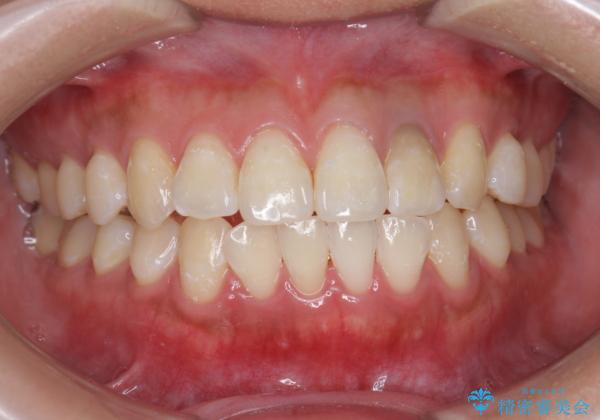

歯の色が自然な感じに白くなり、きれいになったと満足していただけました。